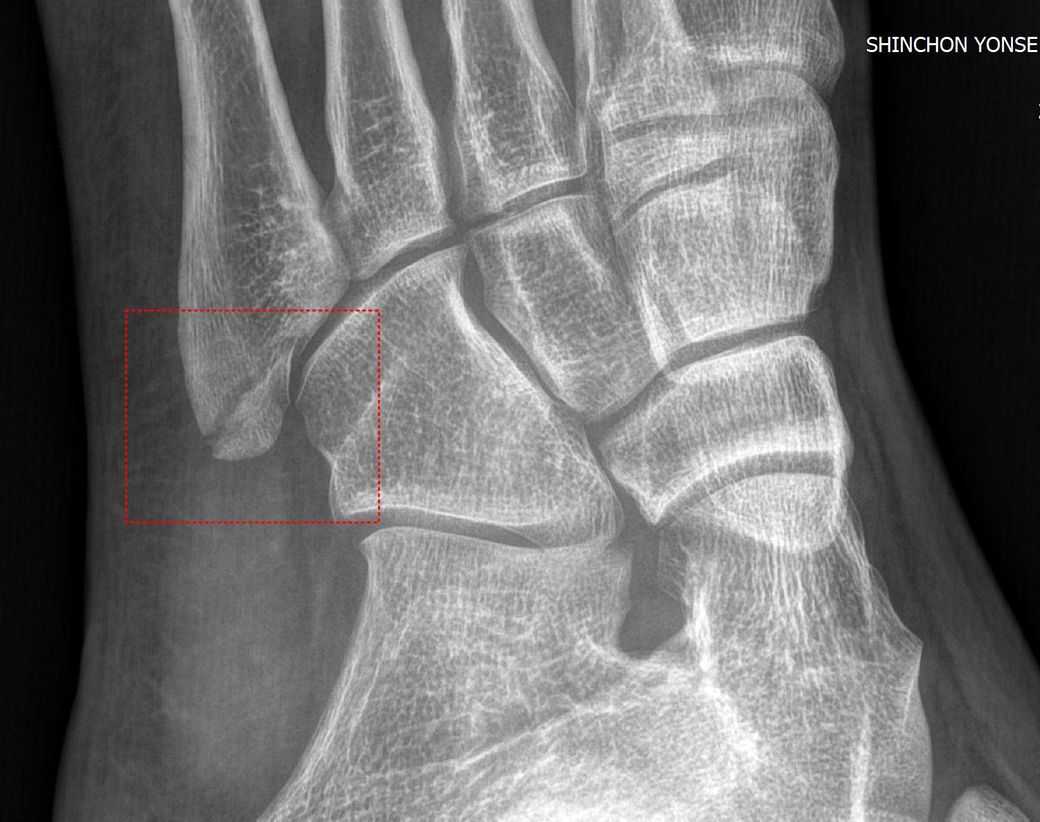

• 3번 째 사진

5번 중족골 기저부 골절에 따른 수술 여부는 단순 주상골 골절인 같은 인대가 뼈를 잡아당기면서 생기는 골절이나 미세한 골절이면 비수술적 치료도 충분히 가능하나 비체중부 골절이나 분쇄골절 시에는 자연 회복이 어렵기 때문에 수술이 필요할 수 있는 상황입니다.

사진상으로는 골절 부위가 뼈의 중심에서 다소 떨어져 있으며, 일부 변위도 있는 것으로 보입니다.

비수술적인 치료도 고려될 수 있지만 아무래도 수술을 하시는게 회복기간 및 예후가 좋을 것으로 생각됩니다.